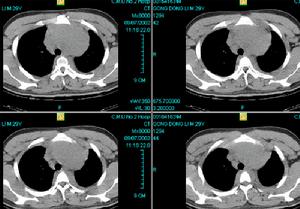

法布里病--透射電鏡檢查3.電鏡檢查:電鏡下顯示上述細胞包含無數圓或卵圓形層狀小體(這些小體被稱為“斑馬小體”或“髓鞘脂影”)對本病診斷很有意義。

本病幾乎所有腎臟細胞均可受累以腎小球毛細血管上皮細胞最甚,受累細胞溶酶體內可見典型的同心圓排列的層板樣異常包涵物為電子緻密的嗜鋨性層狀小體,由於切面不同可呈太陽光環狀、蠕動的絨毛狀或斑馬紋狀結構。多種細胞胞質內有多種形態擴大的溶酶體呈洋蔥皮樣、層板樣緻密實心球狀或空泡狀因此該病的溶酶體改變亦可呈多樣性此外,還可有上皮細胞足突融合基膜灶性增厚等改變